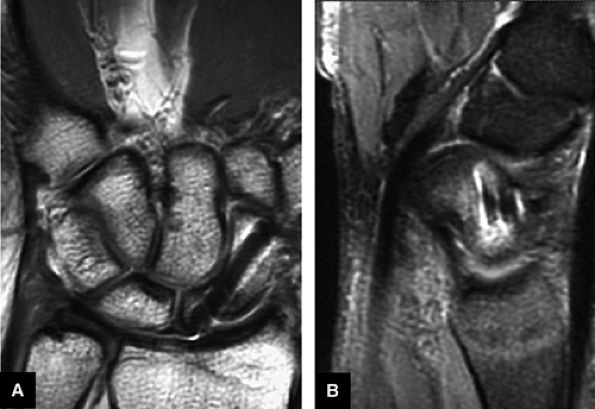

FIGURE 10.43 SCAPHOLUNATE LIGAMENT.

At the site of the radiolunate articulation, the distal articular surfaces of the radius and ulna are usually at the same level (i.e., neutral ulnar variance). Alternatively, the ulna may be relatively long (positive ulnar variance), leading to an ulnar abutment syndrome, or relatively short (negative ulnar variance), as is often seen in Kienböck's disease. The distal radius forms two facets that articulate with the scaphoid and lunate of the proximal carpal row. This articulation of the proximal pole of the scaphoid in the scaphoid fossa is quite congruent, and even a small degree of malrotation of the scaphoid may cause incongruent loading of the articular cartilage and subsequent degeneration (such as that which accompanies a SLAC wrist, as described by Watson and Ryu37). The lunate facet commonly becomes incongruent following distal radius fractures, especially die-punch-type fractures. The interosseous ligaments join the proximal carpal bones at their proximal edges.36

![]() |